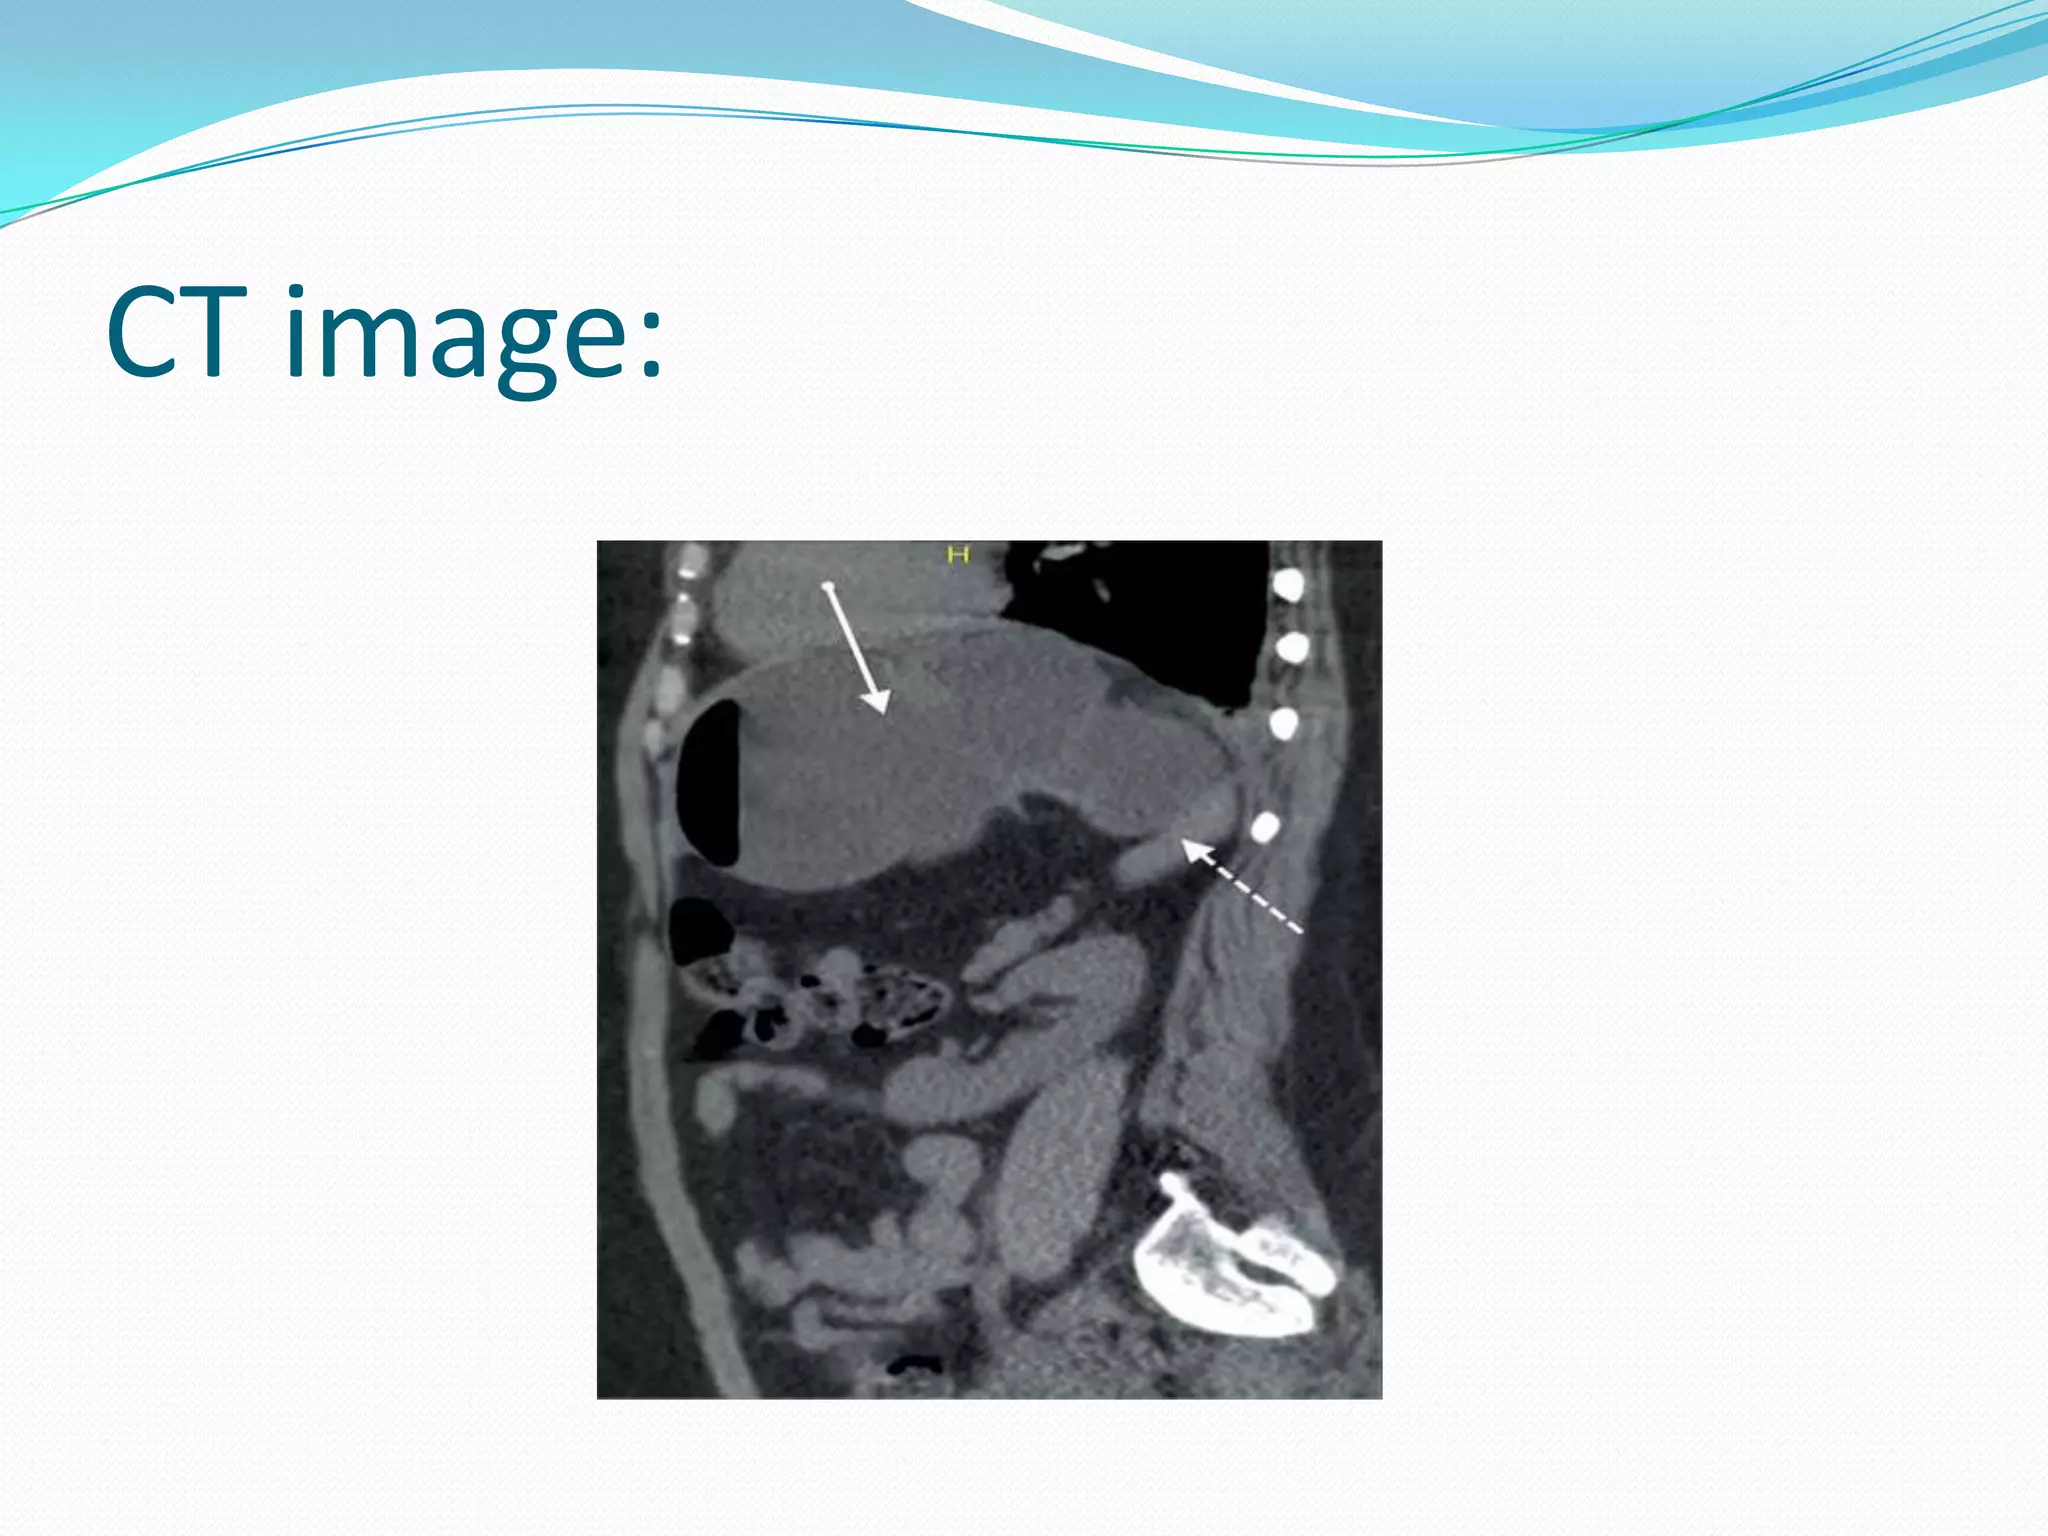

CT image:

Advantage of CT Scan

 detection of gastric pneumatosis and

pneumoperitoneum, suggestive of necrosis and

perforation, respectively

 detection of predisposing factors, e.g. diaphragmatic

defects or hernias, dense adhesions

 detection of other abnormalities associated with

gastric volvulus, viz. wandering spleen, intrathoracic

kidney, malrotation with asplenia

 excluding other extra-gastric or vascular causes of

gastric ischaemia